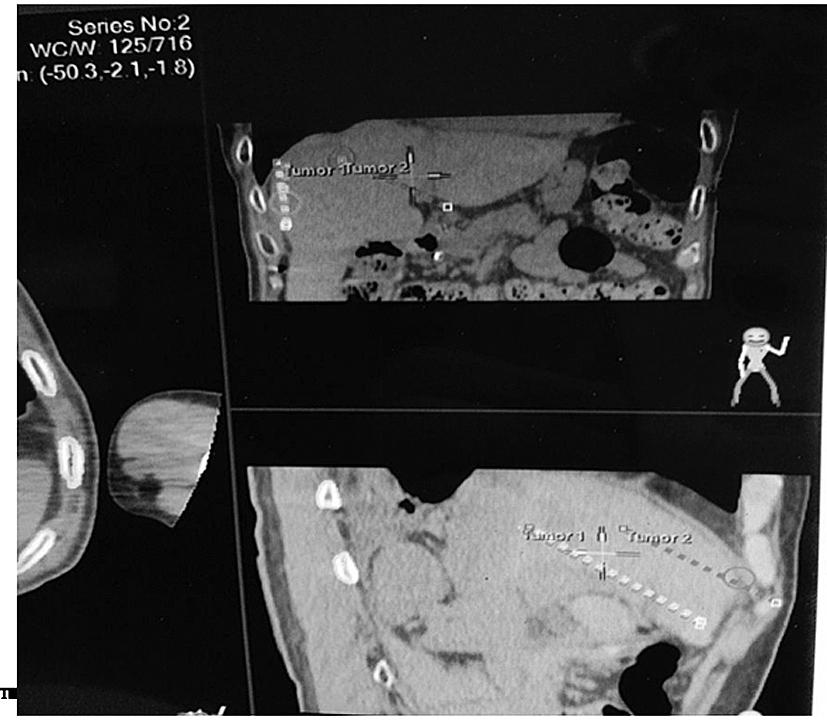

机器人可以设定高难度的进针路线。图中消融近肝包膜及膈顶病灶设计斜行进针路线,避开肺脏和肝内脉管。

制订消融进针计划,设定消融参数,使消融区覆盖瘤体。

3D显示消融针进针路线及消融范围